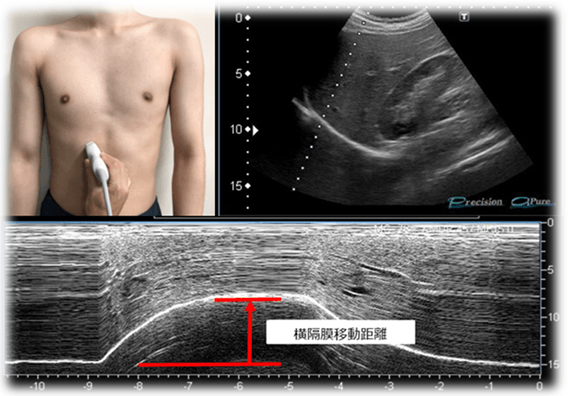

慢性閉塞性肺疾患(chronic obstructive pulmonary disease;COPD)は、主に喫煙などが原因で気道が狭くなり、肺の弾力性が低下する病気です。罹患すると、特に運動時に息をしっかり吐き出せず、肺に空気が溜まることで肺が過度に膨らんで、呼吸を助ける筋肉である横隔膜が正常に機能しなくなり、呼吸困難や息切れの原因となります。国内患者数は年々増加傾向にあり、最新の統計によると、日本における潜在的な患者は約500万人と推定されています。研究グループはこれまでに、超音波画像診断装置を用いた横隔膜移動距離の測定が、慢性閉塞性肺疾患患者の全身の持久力(運動耐容能)等の予測に有用であることを報告してきました。

研究グループは、近畿大学病院に通院する慢性閉塞性肺疾患の患者を対象に、横隔膜機能に対する吸気筋トレーニング(IMT)の効果について調査しました。12週間の呼吸リハビリテーションプログラムの後、在宅治療を中心としたIMTと定頻度の外来呼吸リハビリテーションを受けた患者群と、低頻度の外来呼吸リハビリテーションのみを受けた患者群に分け、超音波画像診断装置を用いて横隔膜の移動距離を測定することで、IMTが横隔膜機能に及ぼす影響を評価しました。その結果、IMTを受けた患者群のみ横隔膜移動距離が増加したことが明らかになりました。また、全身の持久力(運動耐容能)等の改善が見られ、歩行時の呼吸困難感も軽減されました。

参加者は、標準化された12週間の呼吸リハビリテーション(PR)プログラムの後、在宅治療を中心としたIMTと理学療法士が監督する低頻度の外来PRセッション(2週に1回)からなる12週間のIMTプログラムを受けた患者群と、対照として、低頻度の外来PRのみを受けた患者群に分かれました。IMTプログラム実施後、横隔膜移動距離はIMT群で増加しました(50.1±7.6mm→60.6±8.0mm、p<0.001)が、対照群では増加がみられませんでした(47.4±7.9mm→46.9±8.3mm、p=0.10)(いずれもp<0.01)。また、IMT群では運動耐容能(PeakVO2)や運動中の換気応答(VE/VO2,VE/VCO2)、運動時の1回換気量に改善が見られ、歩行時の呼吸困難感も軽減しました。本研究は、12週間の在宅治療を中心としたIMTによりCOPD患者の横隔膜の可動性を改善させられることを証明した初めての研究です。